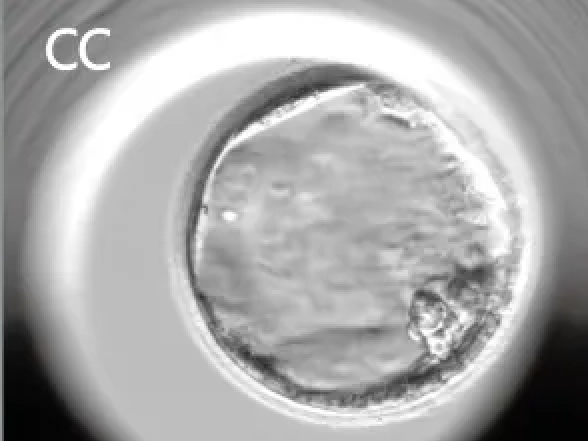

3期:囊腔占满整个胚胎

4期:扩张囊胚(透明带变薄)

5期:开始孵化(部分逸出透明带)

6期:完全孵化(全部逸出透明带)

常见格式:“4AA” “5AB” “3BB” 例如:

-

4AA:非常优质、常被认为是黄金囊胚